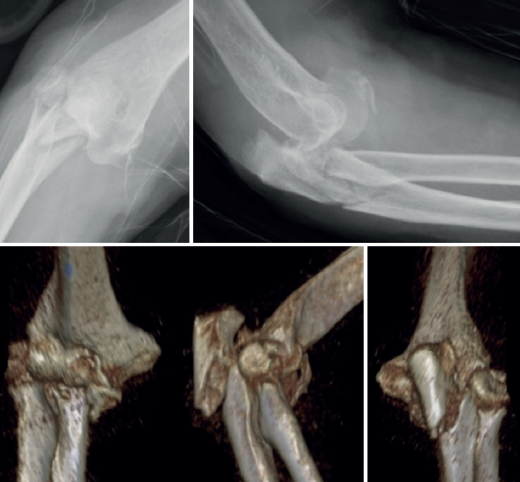

El desplazamiento del cúbito y del radio con respecto al húmero puede ser anterior o posterior tanto en la fractura-luxación transolecraneana como en la fractura-luxación variante de Monteggia (Figuras 2, 3 y 4). En los adultos, las fracturas-luxaciones transolecraneanas anteriores son menos frecuentes que las posteriores y se diferencian más fácilmente de las fracturas-luxaciones variante de Monteggia de tipo I que las fracturas-luxaciones transolecraneanas posteriores, que frecuentemente se confunden con fracturas-luxaciones variante de Monteggia de tipo II. En ambas lesiones existe una fractura intraarticular del olécranon, pueden asociar una fractura y/o luxación de la cabeza del radio y una fractura de la coronoides y, en las fracturas-luxaciones variante de Monteggia de tipo II, puede asociarse una lesión del ligamento colateral lateral(1,2,13,14,15).

Las fracturas transolecraneanas anteriores son consecuencia de un mecanismo de alta energía en el que la tróclea impacta con el olécranon mientras el codo está flexionado, produciendo un desplazamiento anterior del antebrazo con respecto al olécranon, que puede tener una fractura simple o con mayor frecuencia ser conminuta(14). No hay lesión de la articulación radiocubital proximal, ni de la cabeza del radio ni de los ligamentos estabilizadores de la articulación humerocubital y la fractura de la coronoides es menos frecuente que en los casos con desplazamiento posterior. Las lesiones que mayor confusión suscitan son las fracturas-luxaciones transolecraneanas posteriores, que con frecuencia se confunden con las fracturas-luxaciones de Monteggia posteriores, donde el hecho diferenciador es la luxación de la articulación radiocubital proximal en estas últimas y su preservación en las primeras. El mecanismo lesional puede ser de baja energía (por ejemplo, caída de la persona desde su propia altura) en personas de edad avanzada, mayoritariamente mujeres con osteoporosis, o de alta energía (caídas desde grandes alturas o accidentes de tráfico) en jóvenes, que asocian politraumatismo y fracturas abiertas. Las fracturas y/o luxaciones de la cabeza del radio, las fracturas de la coronoides y la afectación de la porción cubital del ligamento colateral lateral son frecuentes en las fracturas-luxaciones transolecraneanas y las fracturas-luxaciones variante de Monteggia con desplazamiento posterior(1,2,13,14,15).